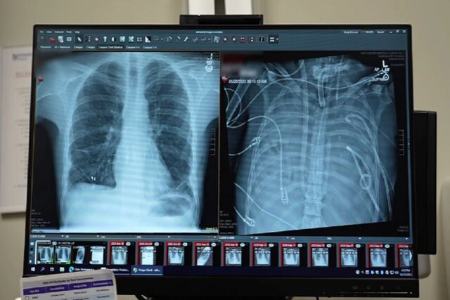

یک مرد ۳۳ ساله بعد از اینکه گروه پزشکی، اعضای بدنش را با یک سیستم ریه مصنوعی خارجی جایگزین کردند که توسعه یافته بود تا او را زنده نگه دارند که بتواند پیوند دو ریه دریافت کند، به مدت ۴۸ ساعت بدون ریه‌هایش زنده ماند.

به گزارش ایسنا به نقل از نیچر، انکیت بهارات، جراح قفسه سینه در دانشکده پزشکی فاینبرگ دانشگاه نورث‌وسترن در شیکاگو، ایلینوی، که به توسعه یک سیستم ریه مصنوعی کمک کرده است، می‌گوید: مواردی وجود داشته است که در آن افراد ریه‌های خود را برداشته‌اند و به یک دستگاه خارجی متصل شده‌اند تا سطح اکسیژن حفظ شود. اما دستگاه‌هایی که در این موارد استفاده شده‌اند، به عنوان ریه مصنوعی حساب نمی‌شوند، زیرا آن‌ها جریان خون را از قلب حفظ نمی‌کنند، به این معنی که قلب نمی‌تواند به طور طبیعی کار کند.

بهارات می‌گوید طراحی گروه او منحصر به فرد است، زیرا جریان خون متعادل و پیوسته به قلب را حفظ می‌کند و خطر لخته شدن خون که می‌تواند سکته قلبی ایجاد کند را کاهش می‌دهد.

وضعیت تهدیدکننده حیات

قبل از قرار گرفتن روی سیستم ریه مصنوعی، این مرد دچار سندرم حاد دیسترس تنفسی شده بود که یک وضعیت اغلب تهدیدکننده حیات است که در آن ریه‌ها نمی‌توانند اکسیژن کافی جذب کنند و این مشکل توسط ویروس آنفلوانزا ایجاد شده بود. سپس او روی ونتیلاتور قرار گرفت، اما دچار عفونت مقاوم به دارو شد. این عفونت باعث شد قسمت‌هایی از ریه‌های او پر از چرک شود و او وارد شوک سپتیک شود که در این مرحله قلب و کلیه‌هایش شروع به از کار افتادن کردند.

بهارات می‌گوید: او خیلی بیمار بود، دچار ایست قلبی شد و در حال مرگ بود. از آنجا که این مرد خیلی بیمار بود که پیوند ریه دریافت کند، گروه پزشکان تصمیم گرفتند ریه‌های او را که منبع عفونت بود، بردارند.

به طور شگفت‌انگیز، مرد شروع به بهبود سریع کرد. در عرض ۴۸ ساعت، او همه داروها برای حمایت از فشار خون را کنار گذاشت، عملکرد کلیه او کاملا بازیابی شد و قلب او به طور طبیعی کار می‌کرد. در این مرحله، مرد پیوند دو ریه را دریافت کرد و سال‌ها بعد هیچ نشانه‌ای از رد عضو یا اختلال عملکرد ریه نشان نداد. اکنون تقریبا سه سال از انجام این کار گذشته است و حال بیمار واقعا خوب است.

اگرچه فناوری‌ به نام اکستراکورپورال ممبران اکسیژناسیون (ECMO)، وجود دارد که می‌تواند کار ریه‌ها را انجام دهد و برای اکسیژن‌رسانی به خون و حذف دی‌اکسید کربن کاربرد دارد، ریه‌های فرد در بدن او نگه داشته می‌شوند که قلب را پایدار نگه می‌دارد. راجرز می‌گوید سیستم جدید به قلب متصل است و نسخه‌ اصلاح‌شده‌ای است که فشار مناسب برای جریان خون به و از قلب را حفظ می‌کند.